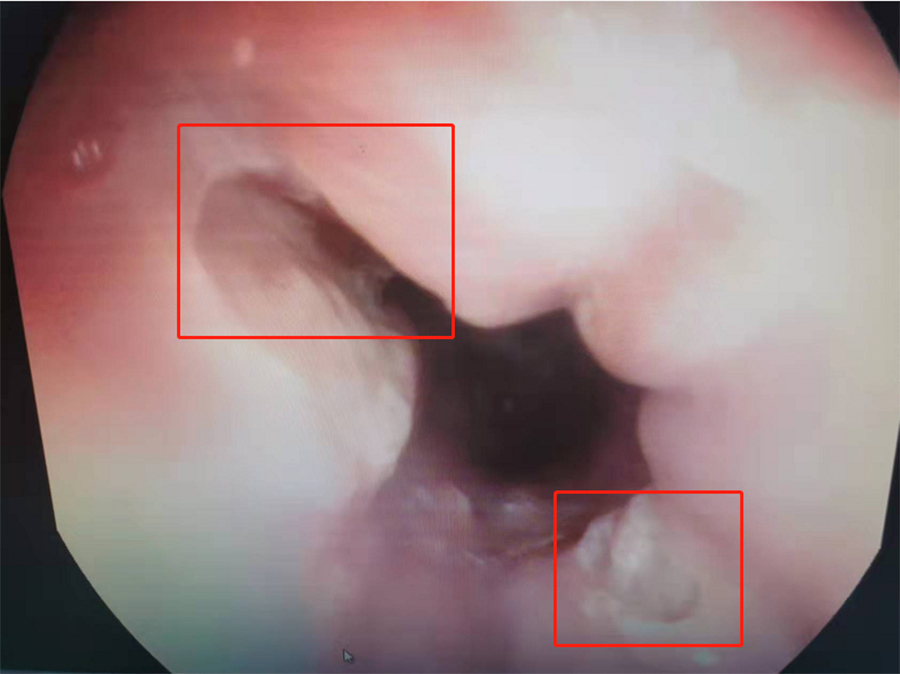

在内镜中心,副主任边鹏为桐桐查体,没发现其上腹胃部区域有压痛。鉴于桐桐腹痛多日,边鹏建议:做胃镜,以明确病因。当胃镜探头进入桐桐食道后,边鹏发现食道下段有两处大面积溃疡,最大处面积达0.3*0.4mm。

临床上,食道溃疡病因很多,常见卡异物后食道损伤,化学性食道损伤、烫伤,部分炎症性肠病也会合并食道溃疡性改变。边鹏根据桐桐食道溃疡对称分布情况,高度怀疑其是误吞异物后造成食道损伤,并有针对性地给出进一步治疗方案:针对食道溃疡,给予口服药物消炎治疗,促进黏膜修复,过一段时间再入院复查。